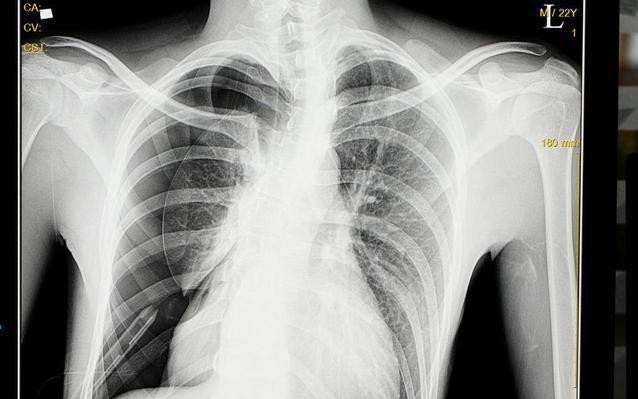

病例:前几天接诊了这样一位患者,小杨今年是高三学生,有一天晚上自习时突然觉得右胸里面一阵剧痛,然后就感觉胸闷,伴有刺激新干咳,小杨以为自己是学习劳累过度,回家后洗漱了一下躺下就睡了。到了半夜咳嗽及胸闷逐渐加重,出现了憋喘症状,家人急忙打了120来到急诊,拍了个胸片,显示右侧自发性气胸,肺压缩百分之90,于是急忙住院做了胸腔闭式引流术,小杨的症状很快得到了缓解。

什么是气胸:气胸是胸外科的常见疾病,正常人的胸腔是密闭的,一旦肺有破口后就会进入空气,导致肺被压瘪,因为肺压瘪后无法再进行气体交换,所以病人感到胸闷。他们常常在跑步、持重物后出现,也有患者在安静状态时发生,上文中的小杨就是这样,气胸严重者甚至可危及生命。